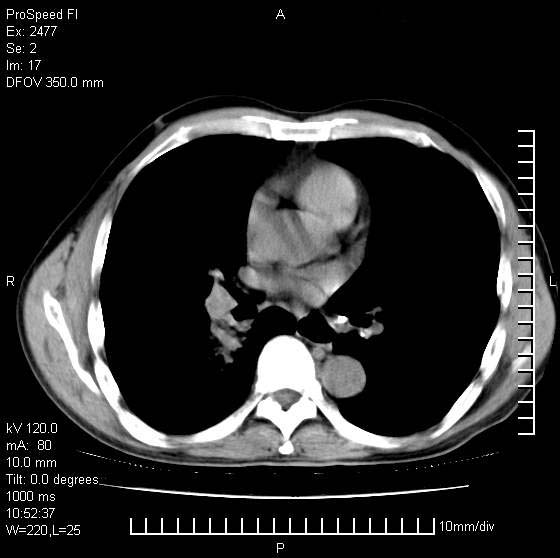

以下是引用天南地北在2007-10-9 14:29:00的发言:[br]1:右上肺结核[br]2:右肺下叶肿块:不支持肺癌,首先考虑炎性病变-肺脓疡可能性大[br]理由:1:临床病史支持,肺脓肿症状不明显应该是不规则服药造成。[br] 2:肿块边缘模糊,周围可见炎性渗出,长毛刺,内见支气管征,不过有点不规则。[br] 我感觉下肺癌这个诊断有点偏左,建议积极抗炎治疗后复查

以下是引用卜一在2007-10-9 15:55:00的发言:[br][br] [br] 1:右上肺结核[br]2:右肺下叶肿块:不支持肺癌,首先考虑炎性病变-肺脓疡可能性大[br]理由:1:临床病史支持,肺脓肿症状不明显应该是不规则服药造成。[br] 2:肿块边缘模糊,周围可见炎性渗出,长毛刺,内见空气支气管征,不过有点不规则。[br] 我感觉下肺癌这个诊断有点偏左,建议积极抗炎治疗后复查![br]支持! [br] [br] [br]

以下是引用wxy7406在2007-10-9 21:02:00的发言:[br]结合临床病史首先考虑感染性病变,但周围型肺癌不能除外,1.患者年龄偏大2.临床有咯血3.(也觉得是最重要的一点)病灶内有偏心性空洞。

以下是引用王仕学在2007-10-9 13:48:00的发言:[br]右下肺周围性肺癌可能性大,最好活检吧

以下是引用hhcckk在2007-10-9 15:18:00的发言:[br]右上肺病灶考虑结核,病灶多种形态并存(纤维化、增殖性病灶并存)[br]右下肺病灶比较难说,个人意见更趋向于“天南地北”的诊断----肺脓肿[br]1、病人有明显的寒战,高热,肿瘤病人很少出现[br]2、病灶周围的肺纹理走向柔和,没有肿瘤病灶常见的集束征[br]3、病灶边缘的毛刺较长,恶性肿瘤多为短毛刺[br]痰中血丝和病人的年龄是两个不利于良性肿块的因素,建议早点活检

以下是引用ydx_74在2007-10-9 15:53:00的发言:[br]右上肺结核,右下中心性肺癌可能大,肺门淋巴结肿大。